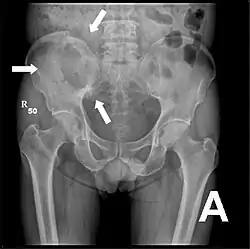

Radio du bassin d'un patient atteint d'un carcinome de la prostate : multiples métastases ostéocondensantes, en particulier sur le sacrum, mais aussi sur l'ilion surtout gauche (à dr. sur l'image), sur la pointe de l'ischion gauche, et sur le fémur proximal gauche. On détecte à l'occasion une arthrose de hanche droite (à g. sur l'image).

Radio du bassin avec métastases ostéolytiques. Les métastases sont sur les deux fémurs et sur le bassin lui-même.